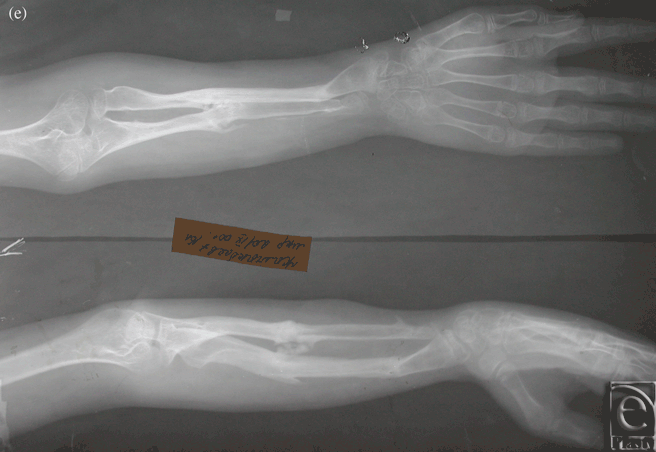

Case 1: Congenital pseudarthrosis forearm

The patient was an 8-year-old boy who suffered from congenital pseudarthrosis forearm type II on both the radius and the ulna. After resection and Ilizarov external fixation/traction, the discrepant 8-cm-long space between the 2 sides was repaired. A secondary free fibula osteoseptocutaneous flap was then harvested from the contralateral side and transferred to the affected side to cover the tissue defects (Figs 1a-1e).

| Figure 1. Case 1: Congenital pseudarthrosis forearm. (a) Preoperative view, (b) Preoperative x-ray, (c) External fixation, (d) The 1-year postoperative view, and (e) A 1-year postoperative x-ray. |